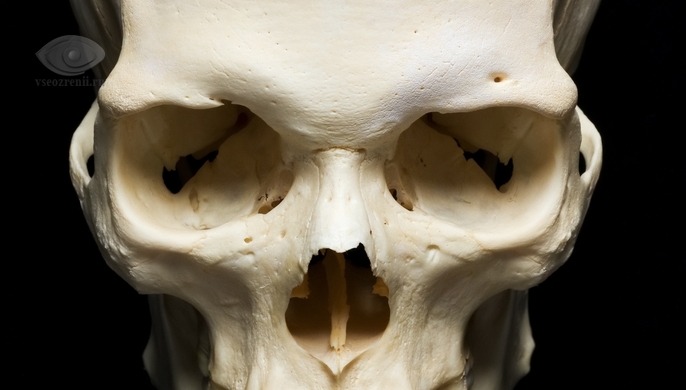

Глазница, или костная орбита, представляет собой костную впадину, защищающую глазное яблоко, вспомогательные структуры, кровеносные сосуды и нервы. Она состоит из четырех стенок: верхней, нижней, наружной и внутренней, которые прочно соединены.

Каждая стенка имеет свои особенности. Наружная стенка самая прочная, внутренняя может повреждаться при незначительных травмах. Верхняя, внутренняя и нижняя стенки содержат воздушные пазухи: лобную сверху, решетчатый лабиринт внутри и гайморовую снизу. Это соседство может приводить к распространению воспалительных процессов из пазух в глазницу. Глазница соединена с полостью черепа через отверстия и щели, что увеличивает риск распространения воспаления в мозг.

По форме глазница напоминает четырехгранную пирамиду с усеченной вершиной, имеющую глубину до 5,5 см, высоту до 3,5 см и ширину входа в глазницу 4,0 см. Соответственно, глазница имеет 4 стенки: верхнюю, нижнюю, внутреннюю и наружную. Наружная стенка сформирована клиновидной, скуловой и лобной костью. Она отделяет содержимое глазницы от височной ямки и является самой прочной стенкой, так что при травмах наружная стенка повреждается крайне редко.

Верхняя стенка образована лобной костью, в толще которой, в большинстве случаев расположена лобная пазуха, поэтому при воспалительных или опухолевых заболеваниях в лобной пазухе, часто они распространяются в глазницу. Вблизи скулового отростка лобной кости расположена ямка, в которой располагается слезная железа. У внутреннего края имеется выемка или костное отверстие — надглазничная вырезка, место выхода надглазничных артерии и нерва. Рядом с надглазничной вырезкой находится небольшое углубление – блоковая ямка, около которой расположен блоковый шип, к которому крепится сухожильный блок верхней косой мышцы, после чего мышца резко меняет направление своего хода. Верхняя стенка глазницы граничит с передней черепной ямкой.

Внутреннюю стенку глазницы, большей частью, формирует тонкая структура — решетчатая кость. Между передним и задним слезными гребнями решетчатой кости имеется углубление — слезная ямка, в которой располагается слезный мешок. Внизу эта ямка переходит в носослезный канал.

Внутренняя стенка глазницы является наиболее хрупкой стенкой глазницы, которая повреждается даже при тупых травмах, за счет чего, практически всегда, в ткани века или самой глазницы поступает воздух — развивается, так называемая, эмфизема. Она проявляется увеличением тканей в объеме, а при ощупывании определяется мягкость тканей с появлением характерного хруста – перемещения воздуха под пальцами. При воспалительных процессах в области решетчатой пазухи, они могут достаточно легко распространяться в полость глазницы с выраженным воспалительным процессом, при этом, если формируется ограниченный гнойник, он называется абсцессом, а распространенный гнойный процесс – флегмоной. Воспаления в глазнице могут распространяться в сторону головного мозга, а значит являться опасными для жизни.

Нижняя стенка образована, в основном, верхней челюстью. От заднего края нижней стенки начинается подглазничная борозда, продолжаясь далее в подглазничный канал. Нижняя стенка глазницы является верхней стенкой гайморовой пазухи. Переломы нижней стенки достаточно часто возникают при травмах, сопровождаясь опущением глазного яблока и ущемлением нижней косой мышцы с ограничением подвижности глаза кверху и кнаружи. При воспалении или опухолях, располагающихся в пазухе верхней челюсти, они также достаточно легко переходят в глазницу.